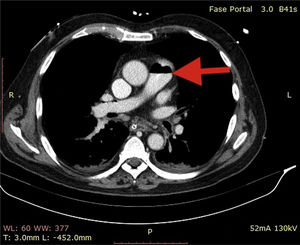

A 72-year-old man, previously independent, was admitted to the emergency department following cardiorespiratory arrest. A chest computed tomography scan (CTS) was requested. During the exam, the patient experienced sudden hypotension (65/20¿;mmHg) and poor peripheral perfusion. The exam was suspended and a fluid bolus was administered, resulting in transient reversal of the condition. Gas was detected in the injection system, which was replaced, and the exam was repeated. The CTS revealed gas embolism with an air-fluid level in the main pulmonary artery (marked with an arrow in Fig. 1), right atrium and right ventricle (marked with an arrow in Fig. 2), as well as in the left upper lobar artery (marked with an arrow in Fig. 3). Due to the venous gas embolism, he was transferred for treatment at a hyperbaric medicine center.